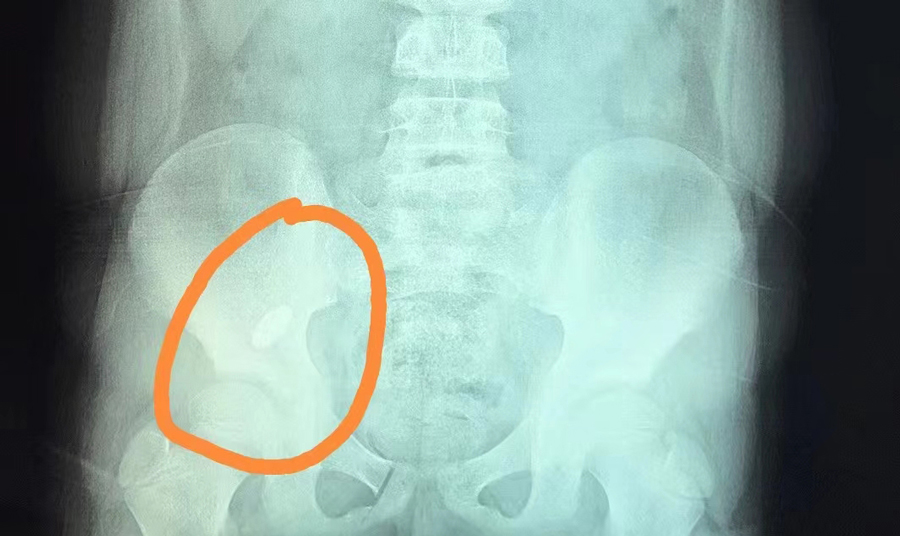

提醒那些认为孩子大了,就可以放松看管的家长:前段时间,长春8岁男孩俊俊(化名)因误吞一颗吸铁石,被家长紧急送到蜜桃视频 。内镜中心副主任边鹏首先对俊俊开具X线检查,确定异物位于右下腹。随后,她综合俊俊身体及异物情况,提出了先观察的建议,看异物是否能被排出,但是在俊俊复查时,发现异物位置并无变化。考虑到异物可能卡在回盲瓣且时间久,会导致局部黏膜损伤,边副主任建议手术取出异物。3月21日13时许,经过术前准备,内镜中心团队为俊俊进行全麻下异物取出手术。随着肠镜的深入,操作医生看到异物一半卡在了阑尾开口处,便利用异物网兜将异物取出,整个过程仅20分钟。阑尾开口处除了有充血水肿外,无其他异常。经过2天的住院治疗,俊俊痊愈出院。

俊俊算是比较幸运的,因为他吞下的是长约40mm、宽约10mm的椭圆形吸铁石,形状比较圆润,取出也算及时,对黏膜损伤不大。边副主任介绍,内镜中心接诊过各种各样的异物病例,总体看没有尖、刺、刃、毒、腐蚀性的异物,多为形状规则圆润且不太大的消化道异物,相对安全一些。如果异物能自然排出最好,反之则需及时通过镜下取出。